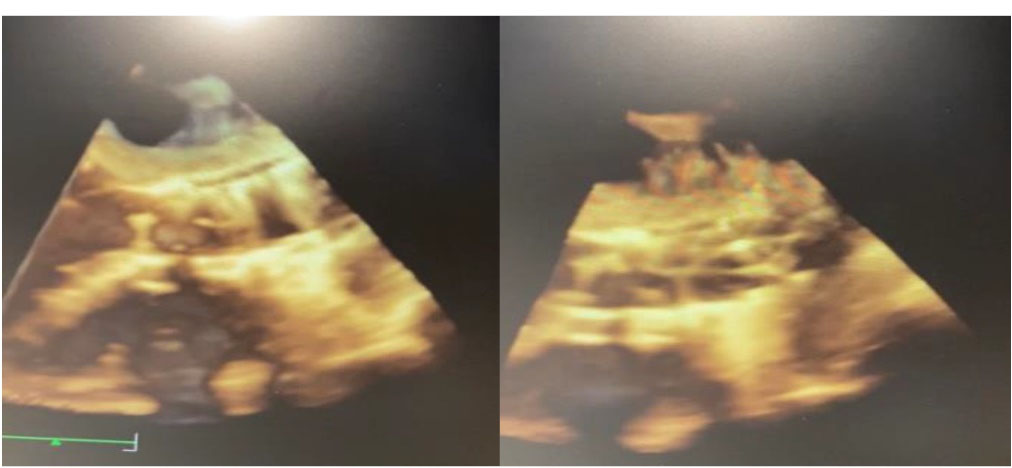

Figure 2.

Ventricular septal defect image after TAVI in transesophageal echocardiography.

3D Transesophageal view of the ventricular septal defect in the closing process.

We present a case of a TAVI procedure using a 29 mm Portico self-expandible valve prosthesis with severe calcific aortic stenosis causing an iatrogenic perimembranous VSD thought to be caused by a calcific nodule located in the left ventricular outflow tract (LVOT). The defect was successfully closed through percutaneous technique using three-dimensional (3D) transesophageal echocardiography (TOE) with the Amplatzer muscular VSD occlude (St. Jude Medical, MN) in another session.

The patient was an active 82-year-old woman (NYHA IV) with shortness of breath at rest. Her comorbidities included hypertension and asthma history. During her examination, she was found to have normal left ventricular (LV) systolic function (ejection fraction; 60%) and severe calcific aortic valve stenosis (aortic valve area: 0.7 cm2; peak / mean gradient: 85/55 mm Hg) on transthoracic echocardiography (TTE). Coronary angiography was found to have normal coronary vessels. The patient with 5.1% STS score was decided to undergo TAVI by our Heart Team. On multi-slice cardiac computed tomography (CT), severe calcification from the aortic valve level and calcified nodule towards the LVOT were noted. Calcific nodule extending to LVOT shown in . The procedure was briefly performed as follows: A 6-F sheath was placed in the right common femoral artery and vein then proglide was inserted. A stiff wire was then inserted through a pig tail catheter. 19 F delivery catheter has been advanced from descending aorta. By performing fast pacing, a nucleus 20×40 mm balloon was predilated and a self-expandable 29 mm Portico prosthesis was implanted. At this stage, there was second grade aortic ınsufficiency (AR) and the prosthesis was postdilated with nucleus 25×40 mm balloon. After the procedure, a very good result was obtained with only minimal insufficiency and elimination of the aortic gradient. No problem developed during the follow-up during hospitalization and no obvious pathology was detected in the post-procedure follow-up echocardiography. However, a pansystolic murmur was detected in the physical examination of the patient with dyspnea at the follow-up 1 month later, and aortic Portico prosthesis (maximum gradient:11 mm Hg, minimal insufficiency) was detected on TTE. However, the right chambers were dilated with significant tricuspid regurgitation and an increased systolic pulmonary artery pressure of 60 mm Hg. In addition, a perimembranous VSD 7 mm was evident beginning from the edge of the prostetic valve, resulting in a significant left-to-right shunt. Based on these findings , it was decided to perform interventional treatment of the defect using the Amplatzer muscular VSD occluder. Right femoral artery and vein canulated using 6-F sheath. A pigtail catheter was passed to the LV. A 0.035 hydrophilic wire and 5-F JR-3.5 catheter were then passed through the VSD to the RV. The wire unintentionally went into the inferior vena cava and the catheter sent over the wire to the inferior vena cava. Then the hidrofilic wire was exchanged with a 0.035 300 cm Noodle wire. The wire was snared in the inferior vena cava and externalized through the right femoral vein. From the right femoral vein a 7-f delivery sheath sent to the ascending aorta through inferior vena cava and the VSD. VSD diameter was measured 7 mm by ventriculography and 8 mm with TOE. Later, 10 mm Amplatzer muscular VSD occluder device was sent through the long sheath, and the first disc was opened in the ascending aorta. Then the system was pulled back to the VSD and the second disc was unsheated (). On 3D-TOE the occluder device was in a correct position, and there was a minimal shunt possibly through the occluder device (). It was disconnected from the delivery cable after confirming that there was no compression or problem with the aortic valve. Two days after the procedure, the device was in a good position, there was mild tricuspid regurgitation and systolic pulmonary artery pressure was 40 mmHg (). After one week of follow-up, the patient was discharged home. It continues to be active with significant improvement in shortness of breath (NYHA I-II) twelve months after the procedure.